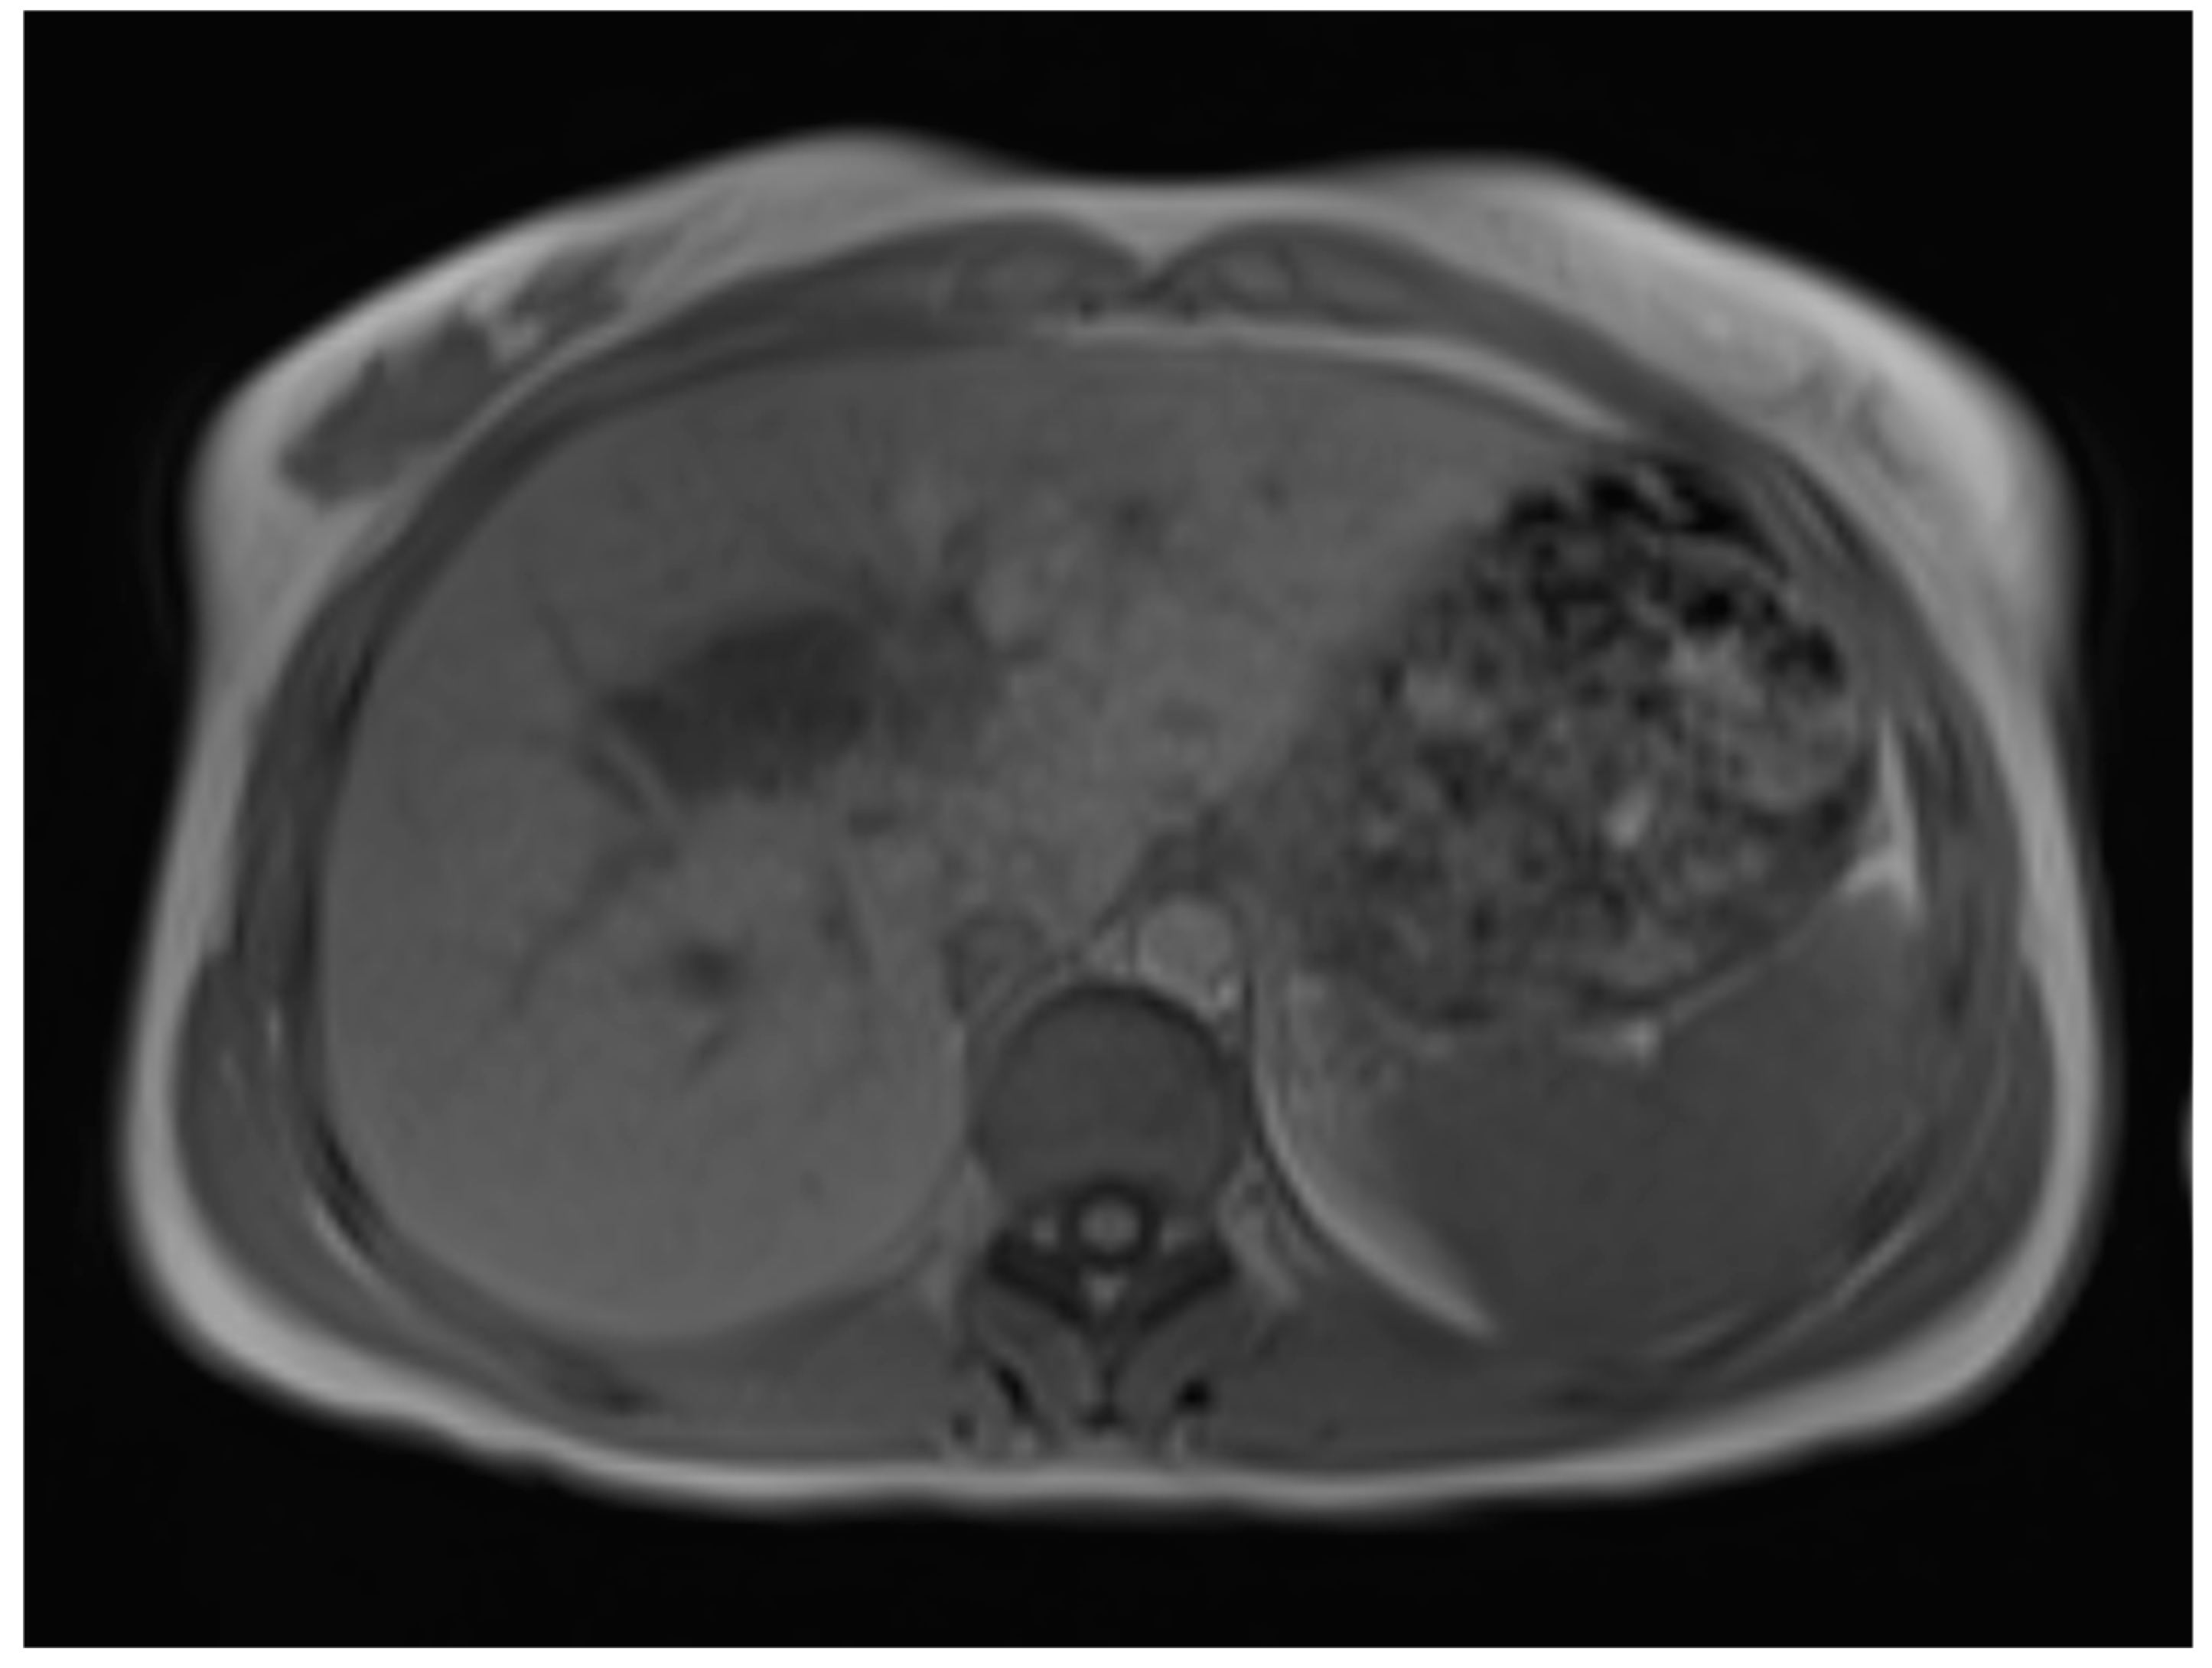

A liver MRI scan confirmed a cystic structure with multiple daughter cysts, hypointense on a T1-weighted image (T1WI), and hyperintense on a T2-weighted image (T2WI), with no solid components, no signs of membrane rupture, and a maximum diameter of 10 cm (craniocaudal) (Figure 1). Additionally, elevated signals on T2WI in the surrounding liver tissue were found. The T1 sequences did not reveal any contrast uptake after 5 (Figure 2), 10, or 20 (Figure 3) minutes post-injection. Furthermore, DWI/ADC mapping indicated a hydatid cyst. The DWI sequences included a trace DWI (Figure 4), an ADC map (Figure 5), and both at b800. Radiomics and AI tools were not involved. The trace DWI showed an area of hypointensity in the region of the cyst that was surrounded by a hypointense layer, depicting the cystic wall. The ADC map revealed hyperintensity within the area, in concordance with a typical depiction of cysts on an MRI scan.

First MRI scan: Axial T2W MRI scan revealing hyperintense areas in liver segment IV, suspicious daughter cysts, and clearly visible septation.

Six months later, a second ultrasound scan and a consecutive MRI scan to follow-up and control the success of the therapy were performed. The ultrasound revealed a decrease in the size of the cyst from 10 cm in maximal diameter to 9 cm and showed multiple circular septations, indicating an involuting cyst (Figure 7). In contrast to the preceding MRI scan, typical T2 hypointense membrane-like structures were observed within the lesion in T2WI. These represented most probably the floating membranes, the typical water-lily sign (Figure 8). T1WI (Figure 9) showed the cyst as a hypointense lesion, but the membranes could only be clearly observed in T2WI. Consecutively, the cyst was classified as WHO-CE3A.

Second MRI scan: Axial T2W MRI scan, where floating membranes forming the water-lily sign after anthelmintic treatment, indicating stage WHO-C3a.